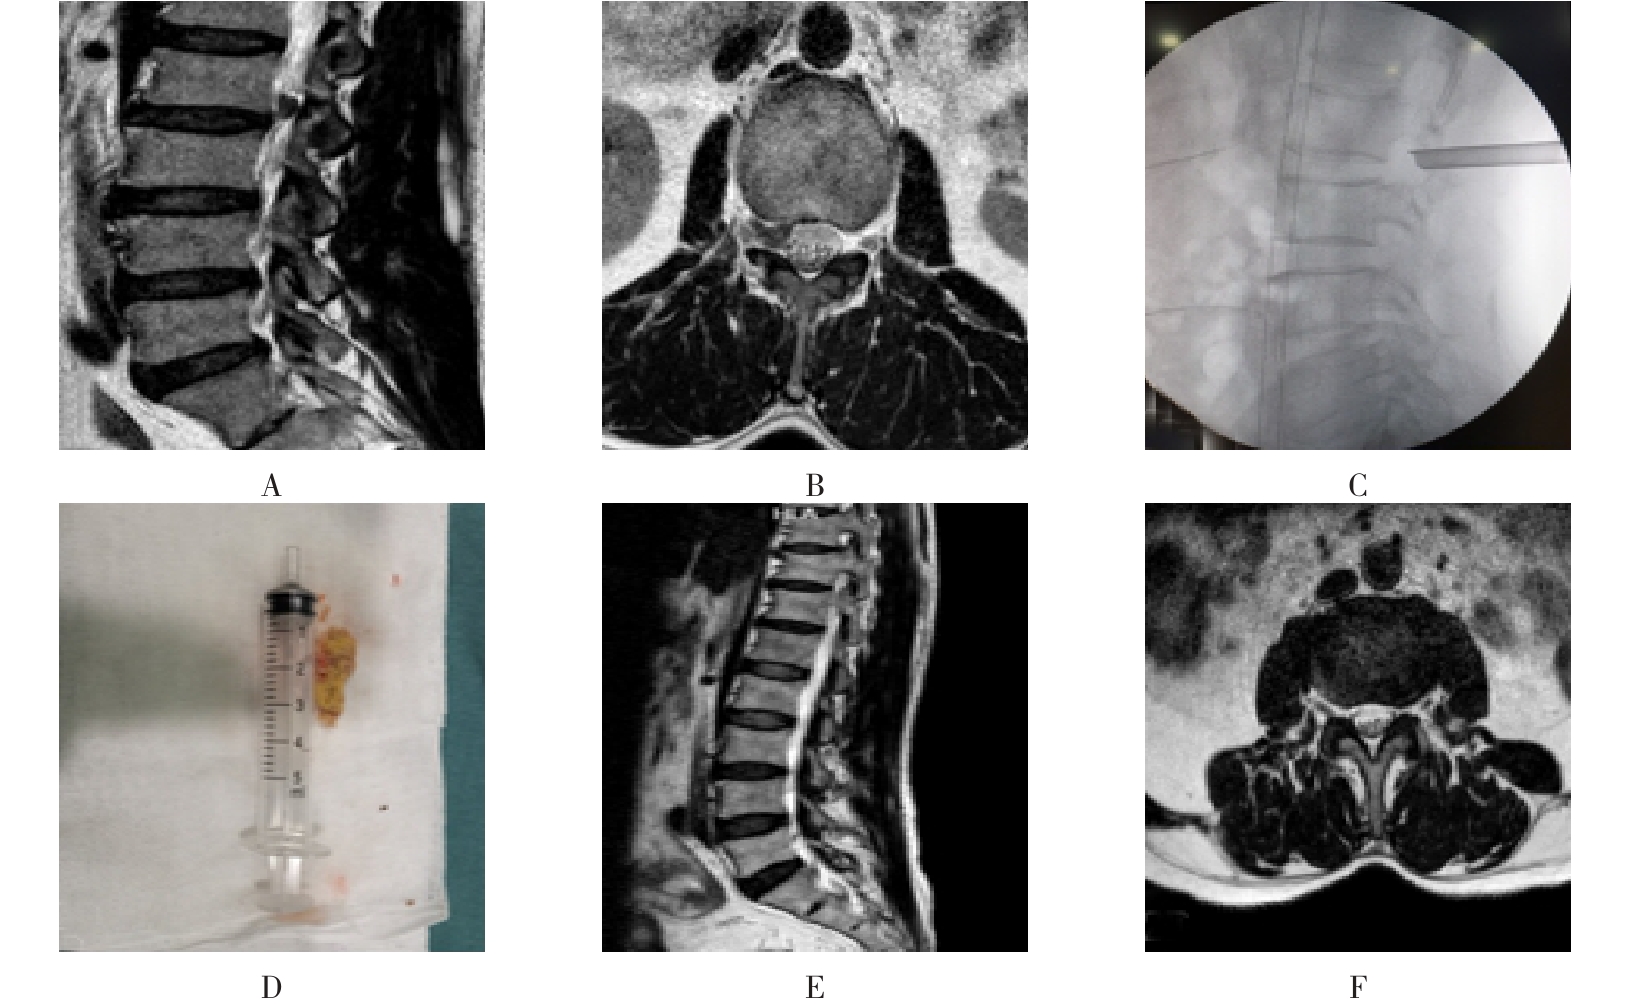

• 单侧双通道内镜与经皮椎间孔镜技术治疗极外侧型腰椎间盘突出症的临床疗效对比

2025, 31(6):9-16. DOI: 10.12235/E20240622

摘要:目的 比较单侧双通道内镜(UBE)与经皮椎间孔镜下髓核摘除术(PTED)治疗极外侧型腰椎间盘突出症(FLLDH)的临床疗效。方法 回顾性分析2021年3月-2023年3月于该院进行治疗的FLLDH患者42例,根据手术方法不同,将患者分为UBE组(18例)和PTED组(24例)。记录并比较两组患者手术时间、术中透视次数、住院时间和围手术期并发症等指标。采用疼痛视觉模拟法(VAS)评估疼痛程度,Oswestry功能障碍指数(ODI)评估功能障碍情况,Macnab评分标准评估临床疗效。结果 UBE组手术时间为(95.56±20.94)min,较PTED组的(78.25±17.23)min长,术中出血量为(69.17±8.95)mL,较PTED组的(23.96±5.89)mL多,差异均有统计学意义(P < 0.05)。UBE组住院时间为(5.67±1.28)d,与PTED组的(5.33±1.05)d比较,差异无统计学意义(P > 0.05)。UBE组术中透视次数为(3.00±0.77)次,明显少于PTED组的(7.42±0.93)次,差异有统计学意义(P < 0.05)。两组患者术后VAS评分和ODI较术前明显降低,差异均有统计学意义(P < 0.05)。术后3 d,UBE组腿痛VAS评分为(3.28±0.58)分及ODI为(41.17±4.30)%,明显低于PTED组的(4.13±0.74)分及(45.50±3.91)%,差异均有统计学意义(P < 0.05),但两组患者术后3个月和1年的VAS评分及ODI比较,差异均无统计学意义(P > 0.05)。两组患者优良率比较,差异无统计学意义(88.9%和87.5%,P = 0.563)。PTED组围手术期出现神经损伤2例,UBE组无神经损伤出现,两组均无感染、复发和大出血等严重并发症发生。结论 PTED与UBE两种手术方式治疗FLLDH均安全和有效。但UBE术中透视次数少,镜下视野更加清晰,神经损伤风险更小。